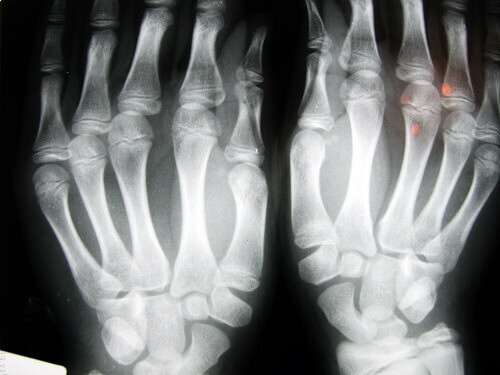

- Artros är vanligast i händerna (70%)

- Som vi alla vet uppsöker vi generellt vår läkare när inte kan härda smärtan längre. Smärtan i händerna är fasansfull, de domnar på natten och små deformiteter uppstår.